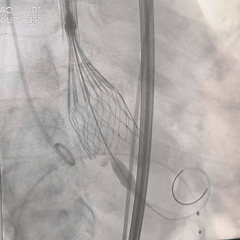

全展开造影,大弯侧位置尚可

左侧位造影,小弯侧位置偏深

回收后调整瓣膜释放位置

全展开造影,瓣膜位置较高

多体位造影,瓣膜位于瓣上